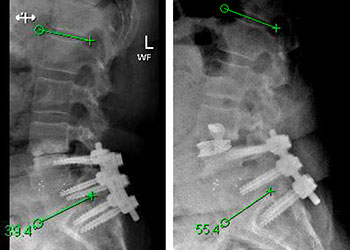

The goals of surgery were to achieve spinal stability, neural decompression, and re-establish a physiologic sagittal alignment. She had co-morbidities that precluded a more conventional open […]

Preop Postop This is a 70-year-old female who has been suffering from progressively worsening back pain for the past decade. She developed a kyphoscoliosis deformity as […]

Figure 1. A) Sagittal T2 MRI demonstrates aggressive hyperintense T3 hemangioma involving the body and posterior elements compressing the thoracic spinal cord (arrows) Figure 1. B […]